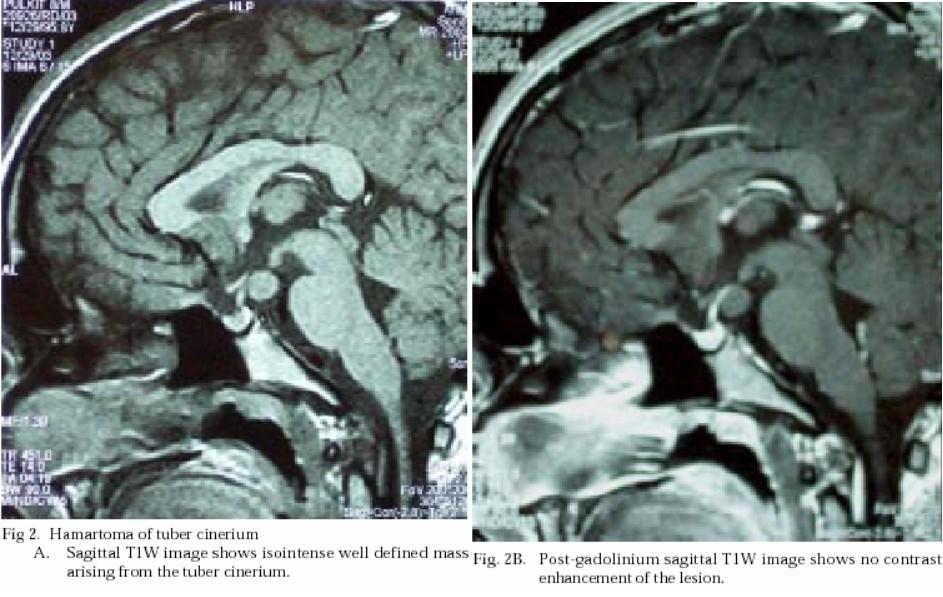

What did this patient present with?

Gelastic “Laughing” Seizures

Precocious puberty

Seizures

Rare calcification

Normal

Rarely increased T2 Flair signal

No enhancement

Trigger Biopsy:

Enhancement

Growth

Different patient, same finding…